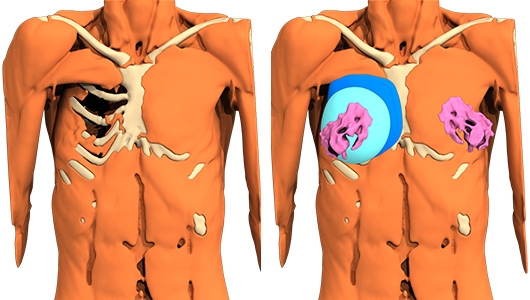

- Einbau eines maßgefertigten Elastomerimplantats, das mittels computergestütztem Design (CAD) hergestellt wurde,

- Passage durch einen S-förmigen axillären Zugang, ohne den alten Zugang zu verwenden,

- Dissektion mit geringer Blutung, die es ermöglicht, einen Hohlraum in Kontakt mit der Brustwand zu schaffen,

- Positionierung des maßgefertigten Implantats, wobei die alte Brustprothese und die dicke Faserkapsel, die sie umgibt, davor liegen bleiben,

Wechsel des Brustimplantats über den axillären Weg: Die kapsuläre Faserebene wird hinten beibehalten, um eine Trennwand zwischen den beiden Implantaten aufrechtzuerhalten und zu verhindern, dass eines über das andere rutscht.

Vorne wird eine neuer, größerer Hohlraum für das neue weiche, mit Silikongel gefüllte Brustimplantat geschaffen. Remodellierung der tuberösen und ptosierten linken Brust mit periareolärer Dermo-Mastopexie.